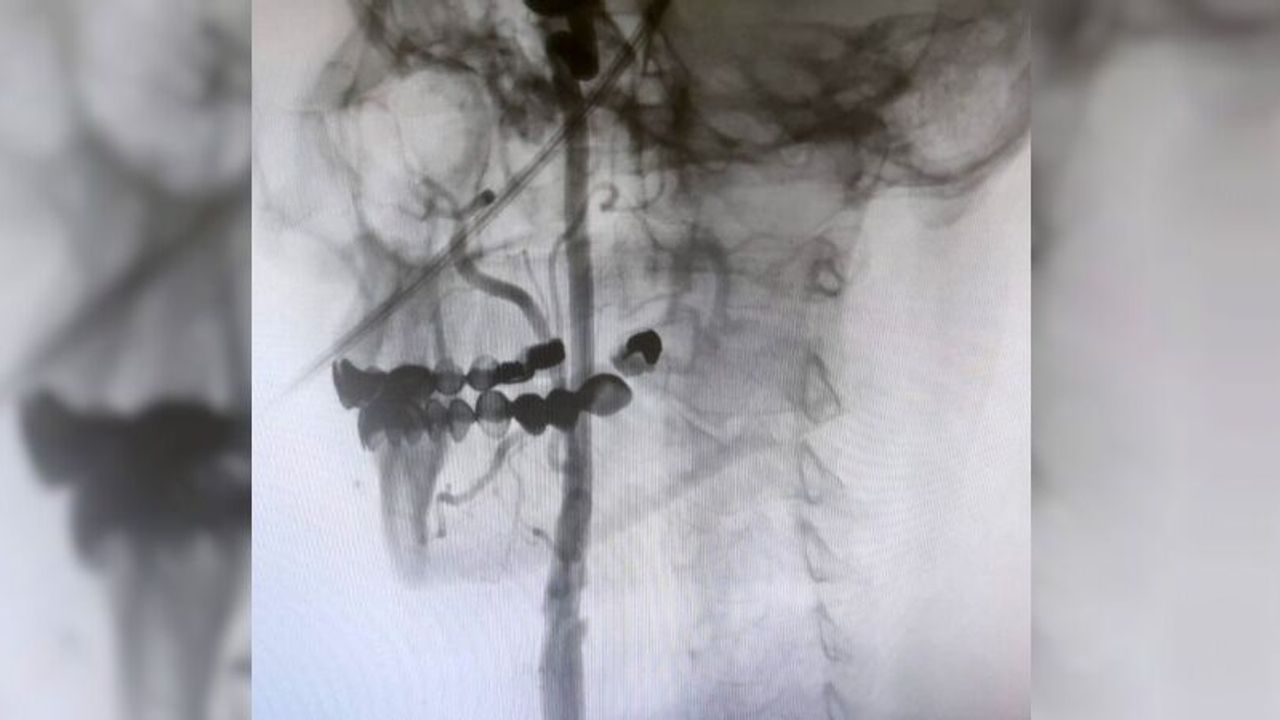

"Boyun damarlarını açma işlemi iki şekilde yapılabilir. Bir karotis endarterektomi dediğimiz ameliyatla bir diğer yöntem ise perkutan girişim dediğimiz stent yöntemiyle açılabilir. Biz kliniğimizde nöroloji ve kardiyoloji olarak bir konsey yapıyoruz. Damarı ciddi tıkalı olan ve buna bağlı felç geçirmiş hastalarda bu konseyde hastaya işlem yapıp yapmama kararı veriyoruz. Verdiğimiz karar çerçevesinde eğer hastaya işlem kararı vermişsek femoral arter dediğimiz kasık arterinden bir şitle 6 ya da 7 F çapında bir şitle ince bir boruyla bu damara giriş yapıyoruz ve boyun damarlarına ulaşıyoruz. Özellikle teller, filtreler ve stentlerle bu damarları açıp hastanın tedavisini gerçekleştiriyoruz. İşlem ameliyatsız olduğu için hastamız ertesi gün rahat bir şekilde problem olmazsa işlemde taburcu olabiliyor bu işlemden sonra. Bu işlemin yapılması için özellikle anjiografinin olduğu girişimsel nöroloji uzmanının ve girişimsel kardiyoloji uzmanının olduğu ve bu konuda yeterli vaka tecrübesine ve deneyime sahip uzmanların olduğu merkezler gerekir. Bunu yapabilmek için belli bir vaka sayısına ulaşmak ve bu konuda tecrübeli olmak gerekiyor. Biz de Manisa Şehir Hastanesi’ndeki girişimsel kardiyoloji ve nöroloji uzmanları olarak bu işlemi kliniğimizde efektif bir şekilde gerçekleştiriyoruz."